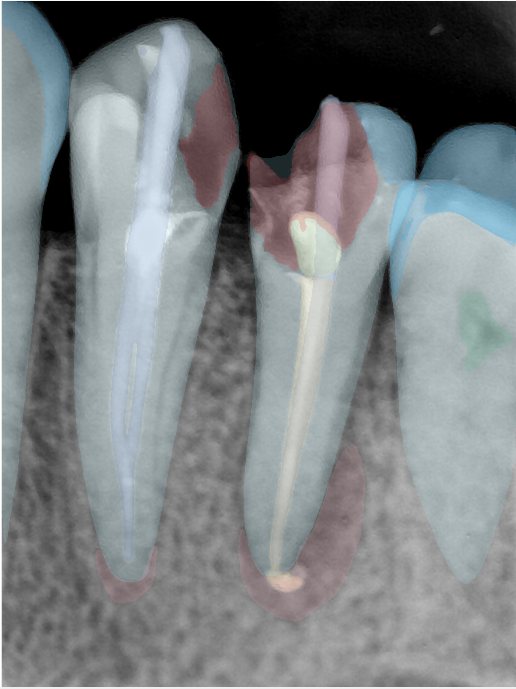

第三版算法分辨率效果比较

| 编号 | 原图 | 第一版 | 第二版 | 第三版 1216x1600 | 第三版 768x1024 | 第三版 1120x1120 |

|---|---|---|---|---|---|---|

| 131315.jpg | ![]() | ![]() | ![]() | ![]() | ![]() | ![]() |

| 131316.jpg | ![]() | ![]() | ![]() | ![]() | ![]() | ![]() |

| 131317.jpg | ![]() | ![]() | ![]() | ![]() | ![]() | ![]() |

| 131318.jpg | ![]() | ![]() | ![]() | ![]() | ![]() | ![]() |

| 131319.jpg | ![]() | ![]() | ![]() | ![]() | ![]() | ![]() |

| 131320.jpg | ![]() | ![]() | ![]() | ![]() | ![]() | ![]() |

| 131321.jpg | ![]() | ![]() | ![]() | ![]() | ![]() | ![]() |

| 131326.jpg | ![]() | ![]() | ![]() | ![]() | ![]() | ![]() |